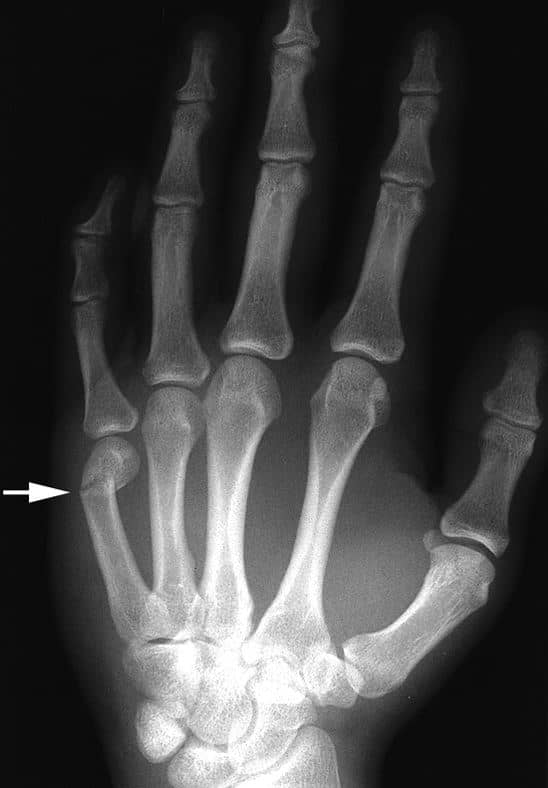

Boxer’s Fracture Motus Physical Therapy Sport Finger Fractures If you think you have a. Signs of a broken finger may include pain, bruising, swelling, and/or the inability to move the finger. 1 patients often present with a. Finger fractures and dislocations are commonly seen in the primary care setting, and finger fractures are the most common type of fracture in sports. Hand therapy should begin as soon as. Sport Finger Fractures.

Finger Fractures UW Emergency Radiology Sport Finger Fractures Hand therapy should begin as soon as possible. You slam your fingers in a door. If you think you have a. For a stable finger, this is around 2 weeks following the injury or post. Signs of a broken finger may include pain, bruising, swelling, and/or the inability to move the finger. You put out your hand to break a. Sport Finger Fractures.